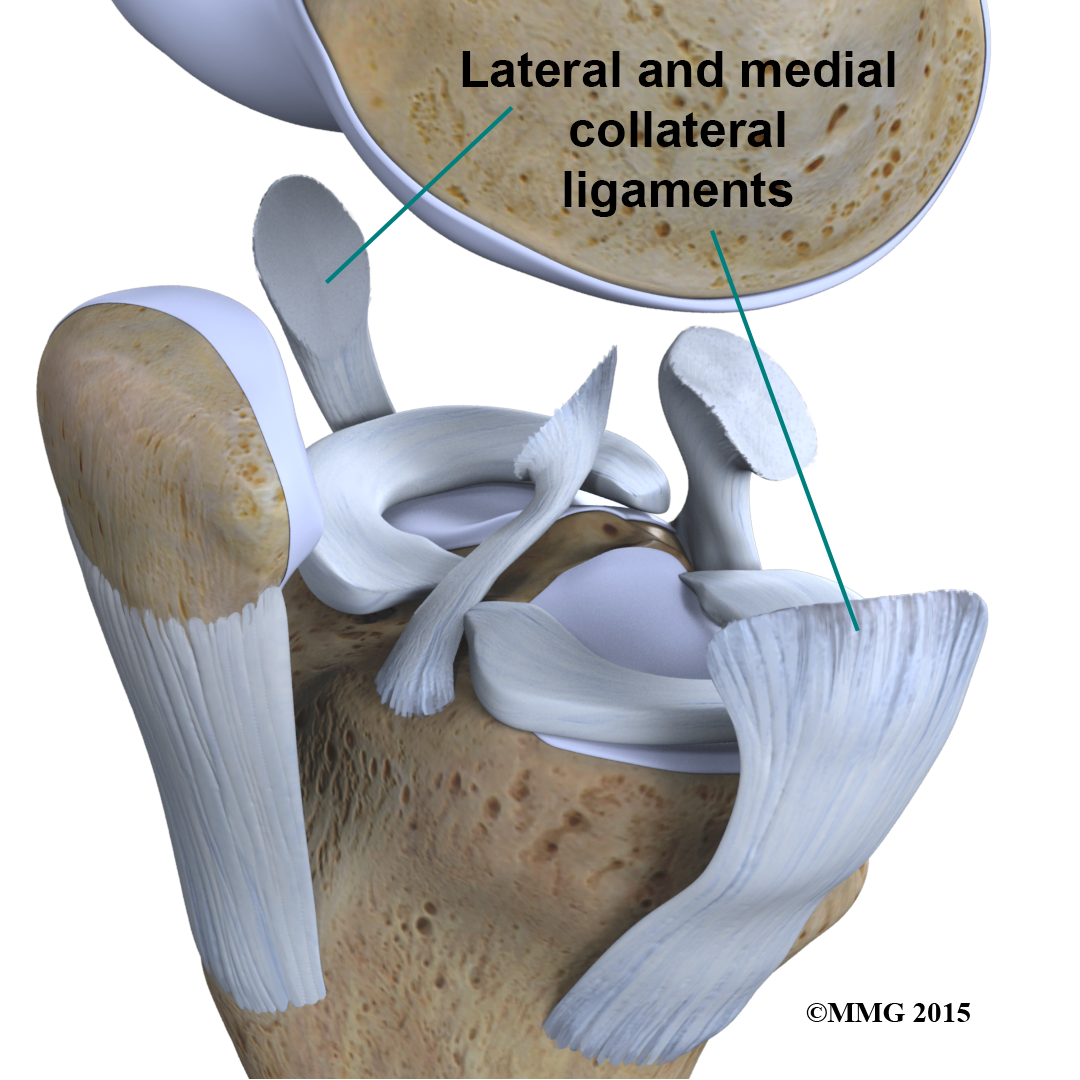

are tough bands of tissue that connect the ends of bones together. Two important ligaments are found on either side of the knee joint. They are the medial collateral ligament (MCL) and the lateral collateral ligament (LCL).

Inside the knee joint, stretch between the femur and the tibia: the anterior cruciate ligament (ACL) in front, and the posterior cruciate ligament (PCL) in back.

The MCL and LCL prevent the knee from moving too far in the side-to-side direction. The ACL and PCL control the front-to-back motion of the knee joint.

The ACL keeps the tibia from sliding too far forward in relation to the femur. The PCL keeps the tibia from sliding too far backward in relation to the femur. Working together, the two cruciate ligaments control the back-and-forth motion of the knee. The ligaments, all taken together, are the most important structures controlling stability of the knee.

Two special types of ligaments called sit between the femur and the tibia. These structures are sometimes referred to as the cartilage of the knee, but the menisci differ from the articular cartilage that covers the surface of the joint.

The two menisci of the knee are important for two reasons: (1) they work like a gasket to spread the force from the weight of the body over a larger area, and (2) they help the ligaments with stability of the knee.

In addition to protecting the articular cartilage, the menisci help the ligaments with stability of the knee. The menisci make the knee joint more stable by acting like a wedge set against the bottom of a car tire. The menisci are thicker around the outside, and this thickness helps keep the round femur from rolling on the flat tibia. The menisci convert the tibial surface into a shallow socket. A socket is more stable and more efficient at transmitting the weight from the upper body than a round ball on a flat plate. The menisci enhance the stability of the knee and protect the articular cartilage from excessive concentration of force.

Taken all together, the ligaments of the knee are the most important structures that stabilize the joint. Remember, ligaments connect bones to bones. Without strong, tight ligaments to connect the femur to the tibia, the knee joint would be too loose. Unlike other joints in the body, the knee joint lacks a stable bony configuration. The hip joint, for example, is a ball that sits inside a deep socket. The ankle joint has a shape similar to a mortise and tenon, a way of joining wood used by craftsmen for centuries.